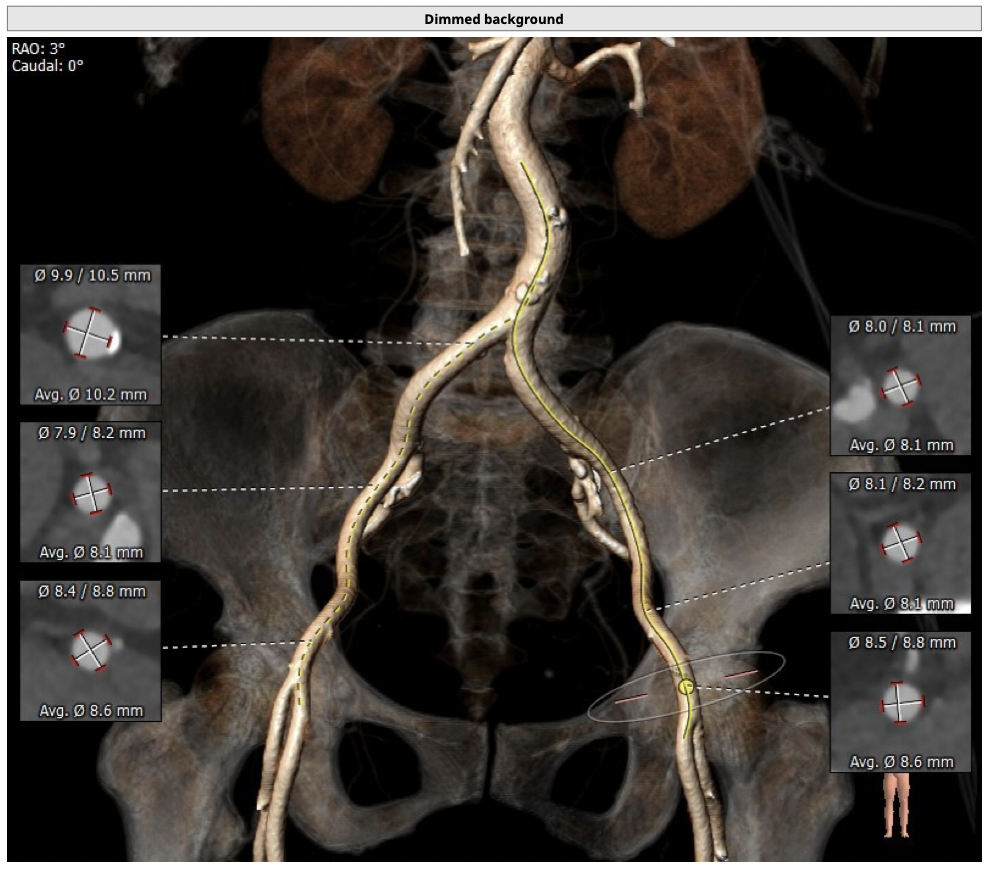

主动脉CT

难点分析:

*患者为TYPE1型二叶瓣,左右融合,重度钙化,融合脊难以推开,瓣膜释放后具有一定瓣周漏风险;

*心脏角度为57°,横位心,输送器过瓣难度增加,瓣膜植入同轴性差,瓣膜释放更易移位,增加了操作的难度;

经分析研判,拟从右侧股动脉穿刺入路,使用20mm球囊预扩,采取downsize手术策略,选用L23号的VenusA-Valve瓣膜,因患者为横位心,瓣膜释放同轴性差,容易发生移位,故采用VenusA-Plus可回收输送系统确保瓣膜的稳定释放,瓣膜释放后结合造影和超声情况,决定是否后扩。